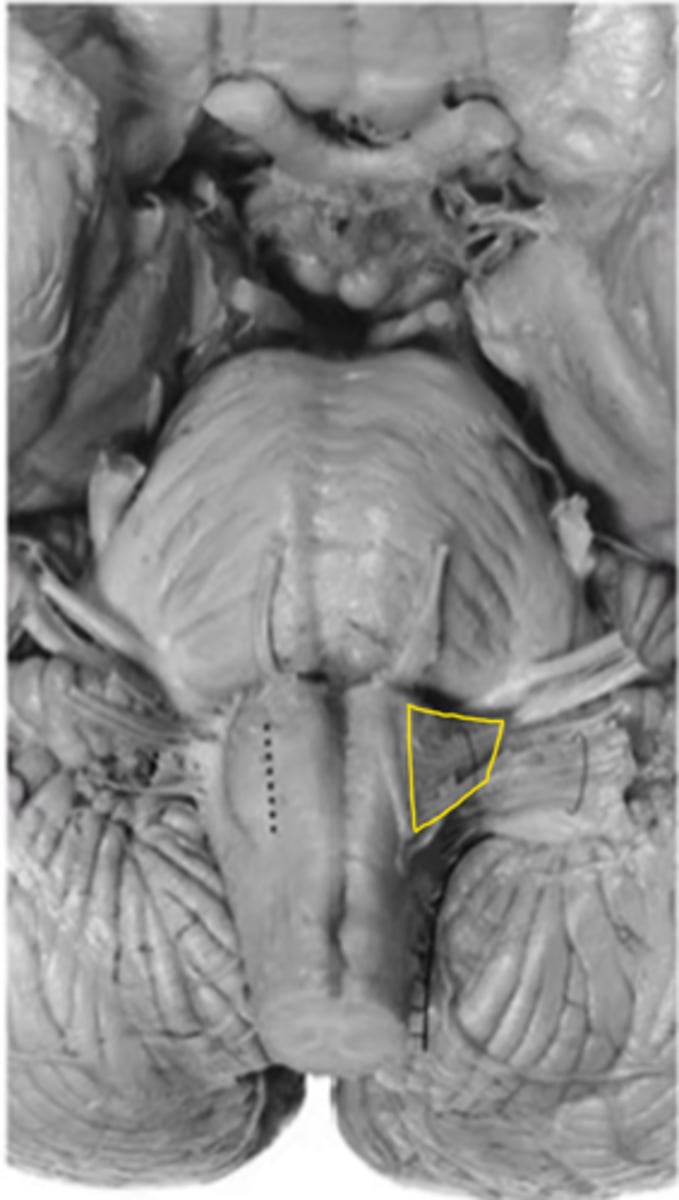

medulla

ID the area

medullary pyramids

ID the structure

anterior median sulcus

olive

pre-olivary sulcus

vestibulocochlear nerve

ID the nerve

glossopharyngeal nerve

vagus nerve

hypoglossal nerve

spinal accessory nerve

fourth ventricle

ID the space

open medulla

closed medulla

ID the brainstem level